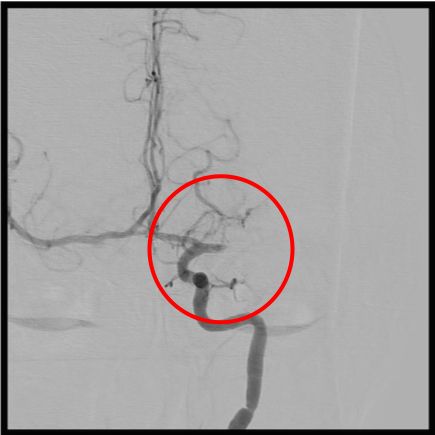

脳底動脈閉塞

術前の造影写真です。〇内で脳底動脈に血栓が詰まり完全閉塞しています。

術後の造影写真です。閉塞していた脳底動脈は完全に再開通しています。